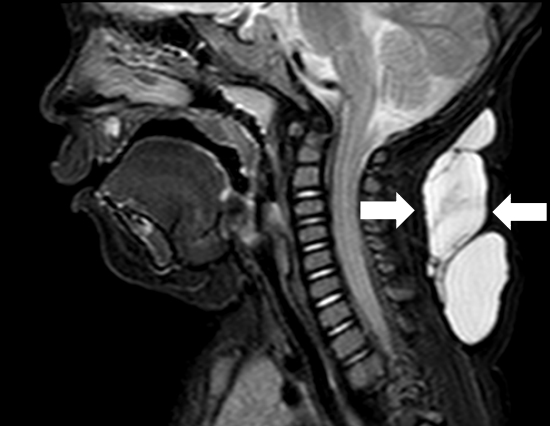

超声难以确诊的病例,或病变周围结构较复杂(如在颈部、纵隔等部位)以及位置较深(如在腹腔、盆腔等部位)治疗难度大、风险高时,往往需加做磁共振检查,更精确评估病情。当影像学检查难以诊断时,也可行诊断性穿刺,若穿刺抽出淡黄色清亮淋巴液即可诊断为淋巴管畸形,若抽出陈旧性血液结合细胞学检查可诊断为淋巴管瘤伴出血。

淋巴管囊肿磁共振检查

纵隔巨大淋巴管畸形压迫气管影响呼吸